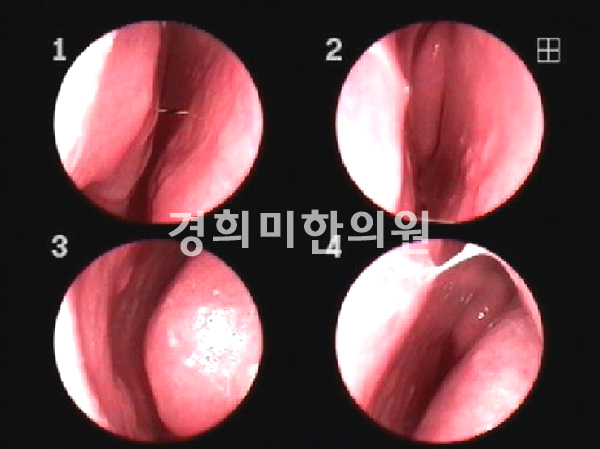

경희미의원 코내시경, 비내시경, 경상코점막의 발적을 관찰하여 2차 세균 감염이 일어나지 않을 경우 점액기로 옮김과 동시에 호전됩니다.통상적으로 증상이 사라지기까지 5~10일 소요됩니다.

급성 중이염(좌), 삼출성 중이염(우)

편도염 만약 급성 비염의 카타르기가 지나 2차 세균 감염이 되면 끈적끈적한 노란 콧물과 함께 코가 막혀서 후비루가 심해집니다.더 악화되면 부비강염, 중이염, 인두편도염, 기관지염, 폐렴, 장염 등의 합병증이 동반될 수 있습니다.이러한 합병증은 면역력이 저하된 환자나 어린이에게 잘 나타나므로 주의가 필요합니다.